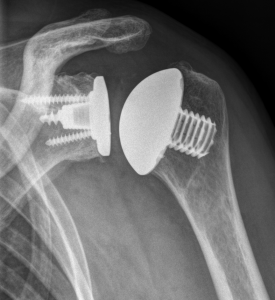

Verschiedene Schultergelenkserkrankungen können den Einbau eines künstlichen Schultergelenkes erforderlich machen. Der Anlass für solch einen Eingriff sind neben den sichtbaren Veränderungen des Gelenkes im Röntgenbild oder im CT die Beschwerden des Patienten, wobei in erster Linie der starke Ruhe- und Belastungsschmerz zu nennen ist, der eine mehr oder weniger regelmäßige Einnahme von Medikamenten erforderlich macht.

Schultergelenksprothesen gibt es seit über 50 Jahren. Gerade in den letzten 20 Jahren hat die Schulterendoprothetik große Fortschritte gemacht. Bei der schmerzhaften Zerstörung des Schultergelenkes durch Arthrose (Gelenkverschleiß), rheumatoide Arthritis (rheumatische Gelenkentzündung), Oberarmkopfnekrose (Absterben des Oberarmkopfes) oder Oberarmkopfbruch ist es heute mit gutem Erfolg möglich, die Gelenkflächen von Oberarmkopf und Schulterpfanne durch Prothesen aus Titan und Polyethylen zu ersetzen. Die Indikation zur Implantation einer Schultergelenksprothese wird gestellt bei:

In diesem Fall kann das Gelenk durch ein sog. inverses Prothesen-System nach Prof. Paul Grammont ersetzt werden. Hierbei wird eine „Halbkugel“ (Glenosphäre) auf die ursprüngliche Pfanne aufgeschraubt und eine konvex geformte „Humeruspfanne“ im Oberarmknochen fixiert (Abb. 48). Der Oberarm wird dadurch wieder nach „unten“ verlagert und die Funktion des M. deltoideus wird verbessert (Abb. 49).